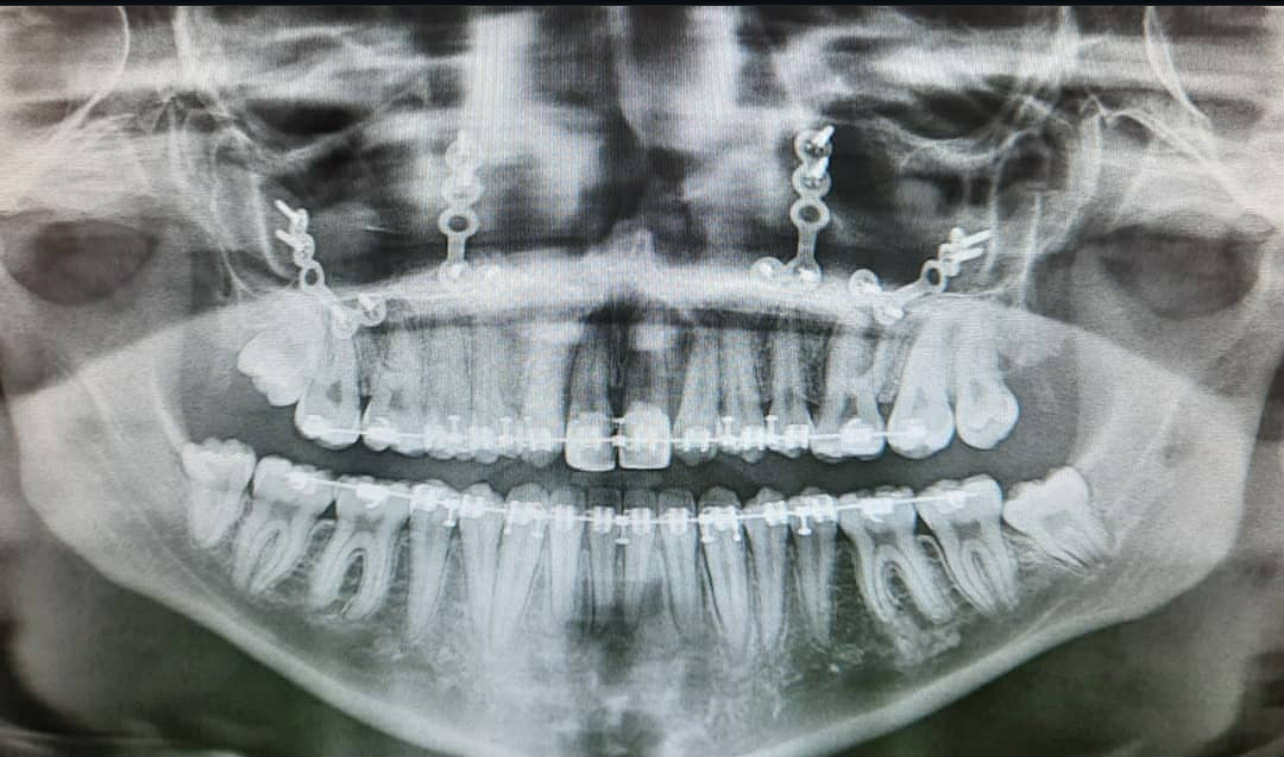

I have had 7 surgeries as treatment for my Cleft Lip. My first surgery was at 14 weeks old, and my most recent surgery was in 2023, when I was 21 years old. I have had a hip-to-face bone graft, Lefort 1 Maxilla Advancement (I have attached an x-ray image of this), and septorhinoplasty, as some examples of my more recent surgeries. I also had two rounds of braces, 1 year between 9 and 10 years old, and 4.5 years between 17 and 20 years old (total of 5.5 years of braces over a 11-year period). I had ongoing orthodontic care from age 8 to age 20. I received some speech therapy, although only a few sessions. The ‘worst’ surgery to recover from was definitely my Maxilla Advancement. I was on a puree diet for two weeks, and then a soft diet for a further 2 weeks. My mouth was banded shut, and I had to brush my teeth with a baby toothbrush because my normal one might have broken the stitches. The pain was dull but constant, and I literally couldn’t recognise myself in the mirror for months afterward as the swelling went down slowly. I love the result and would do it all over again if I had to, but it was the most intensive healing process I can remember.

Teeth X-ray of a girl with cleft lip and palate